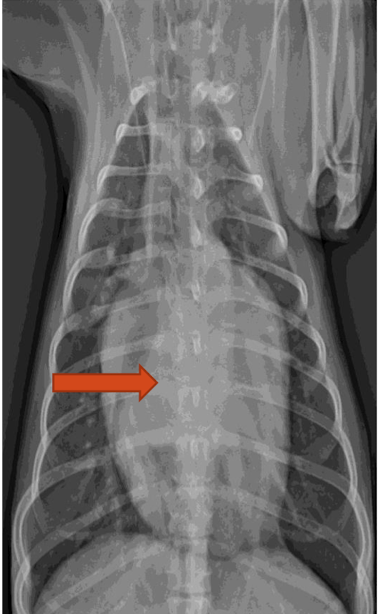

What is the arrow pointing to?

intra-capsular swelling